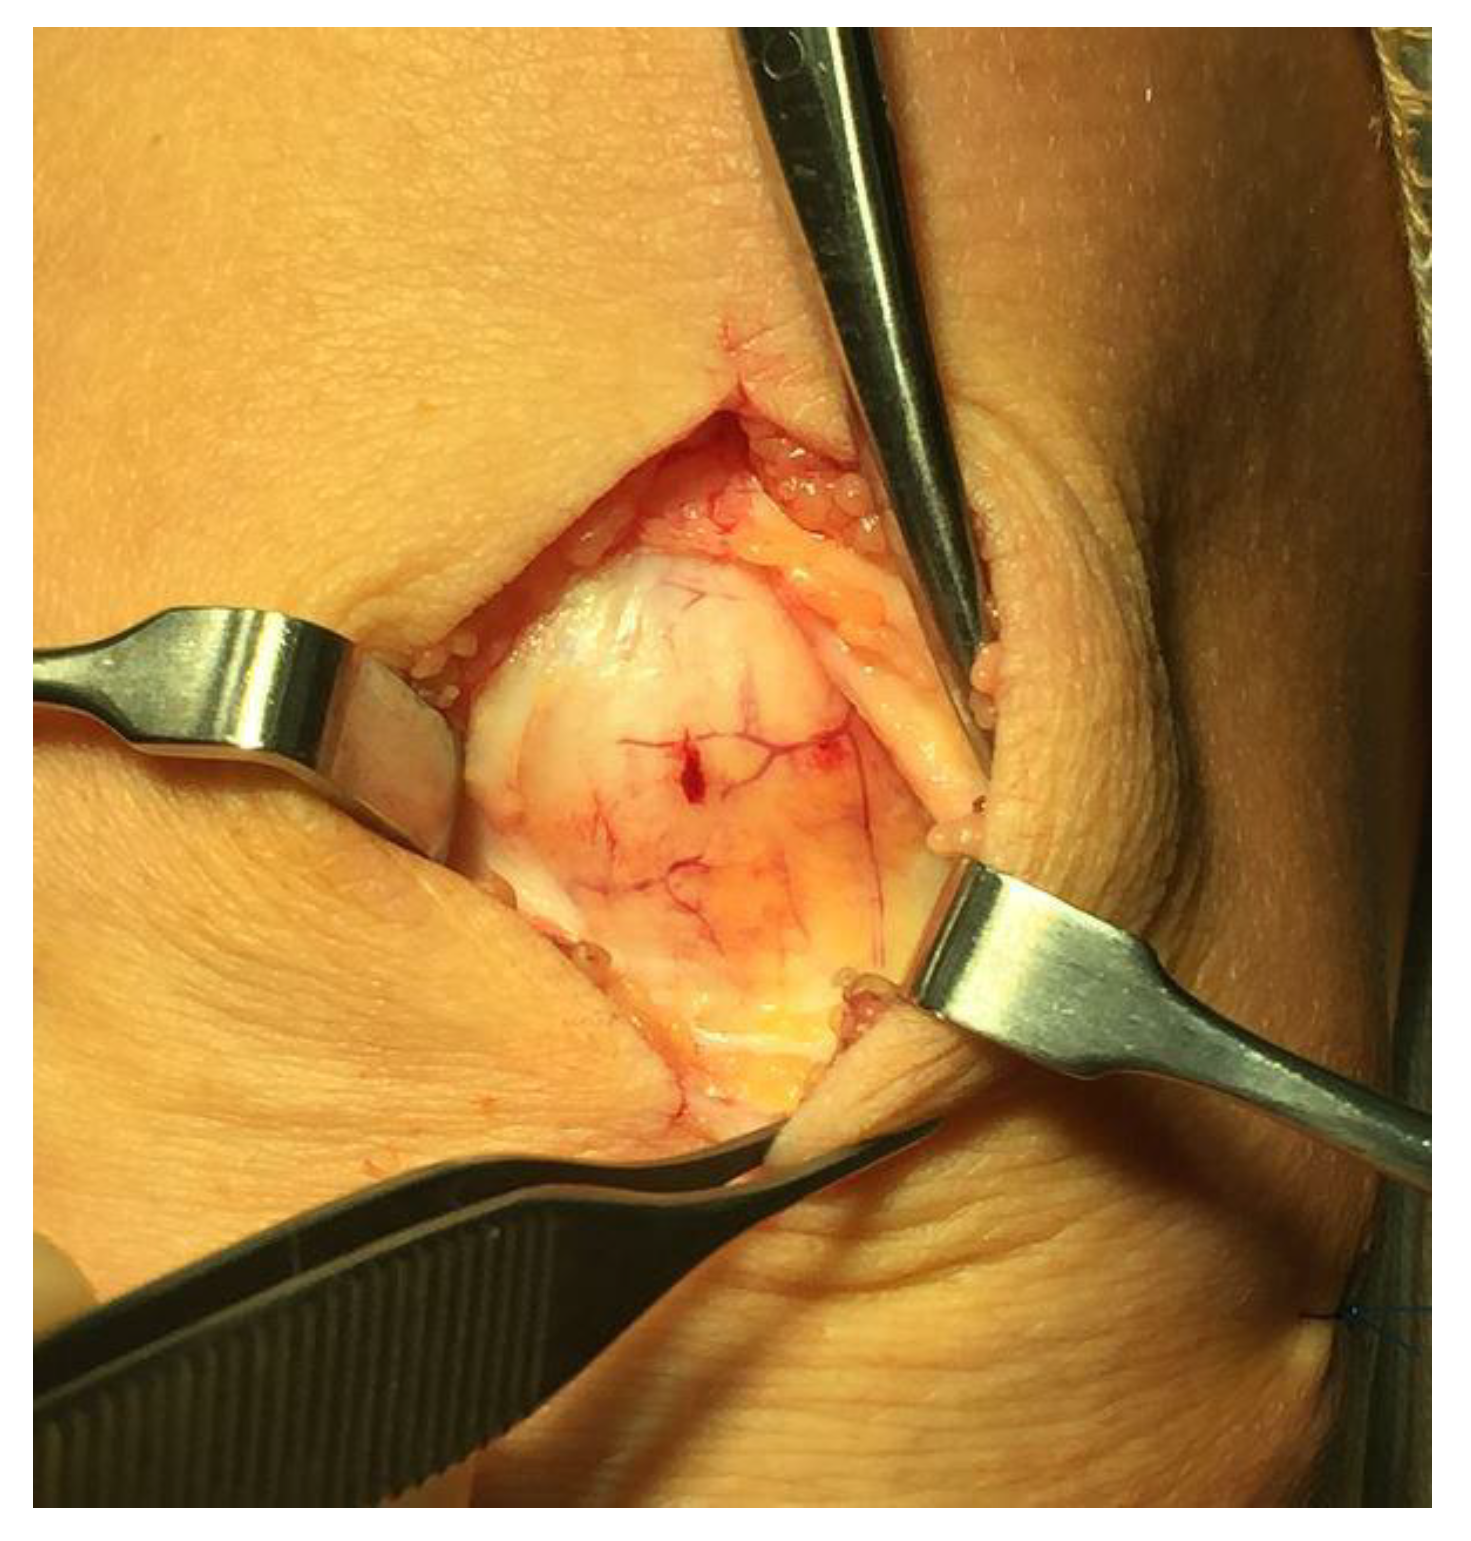

All patients underwent deleted words ultrasound (US) and Doppler (DP)-guided arthroscopic shaving and also open superficial scraping deleted words (Figure 2) [6]. Tissue sections from the superficial peritendinous tissue of the patellar tendon were analyzed for morphology and innervation patterns.

Figure 2. Surgical inspection of the superficial peritendinous tissue. Richly vascularized fatty tissue can be observed.